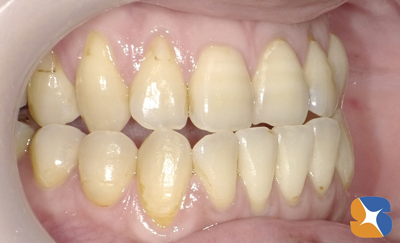

20代の看護師さん。主訴は「矯正を始めるが、『事前に親知らずの抜歯を済ませておくように』と言われた」でした。

矯正前のお口の状態。いち早く矯正を始めるため、抜歯を急がれていることも納得できます。